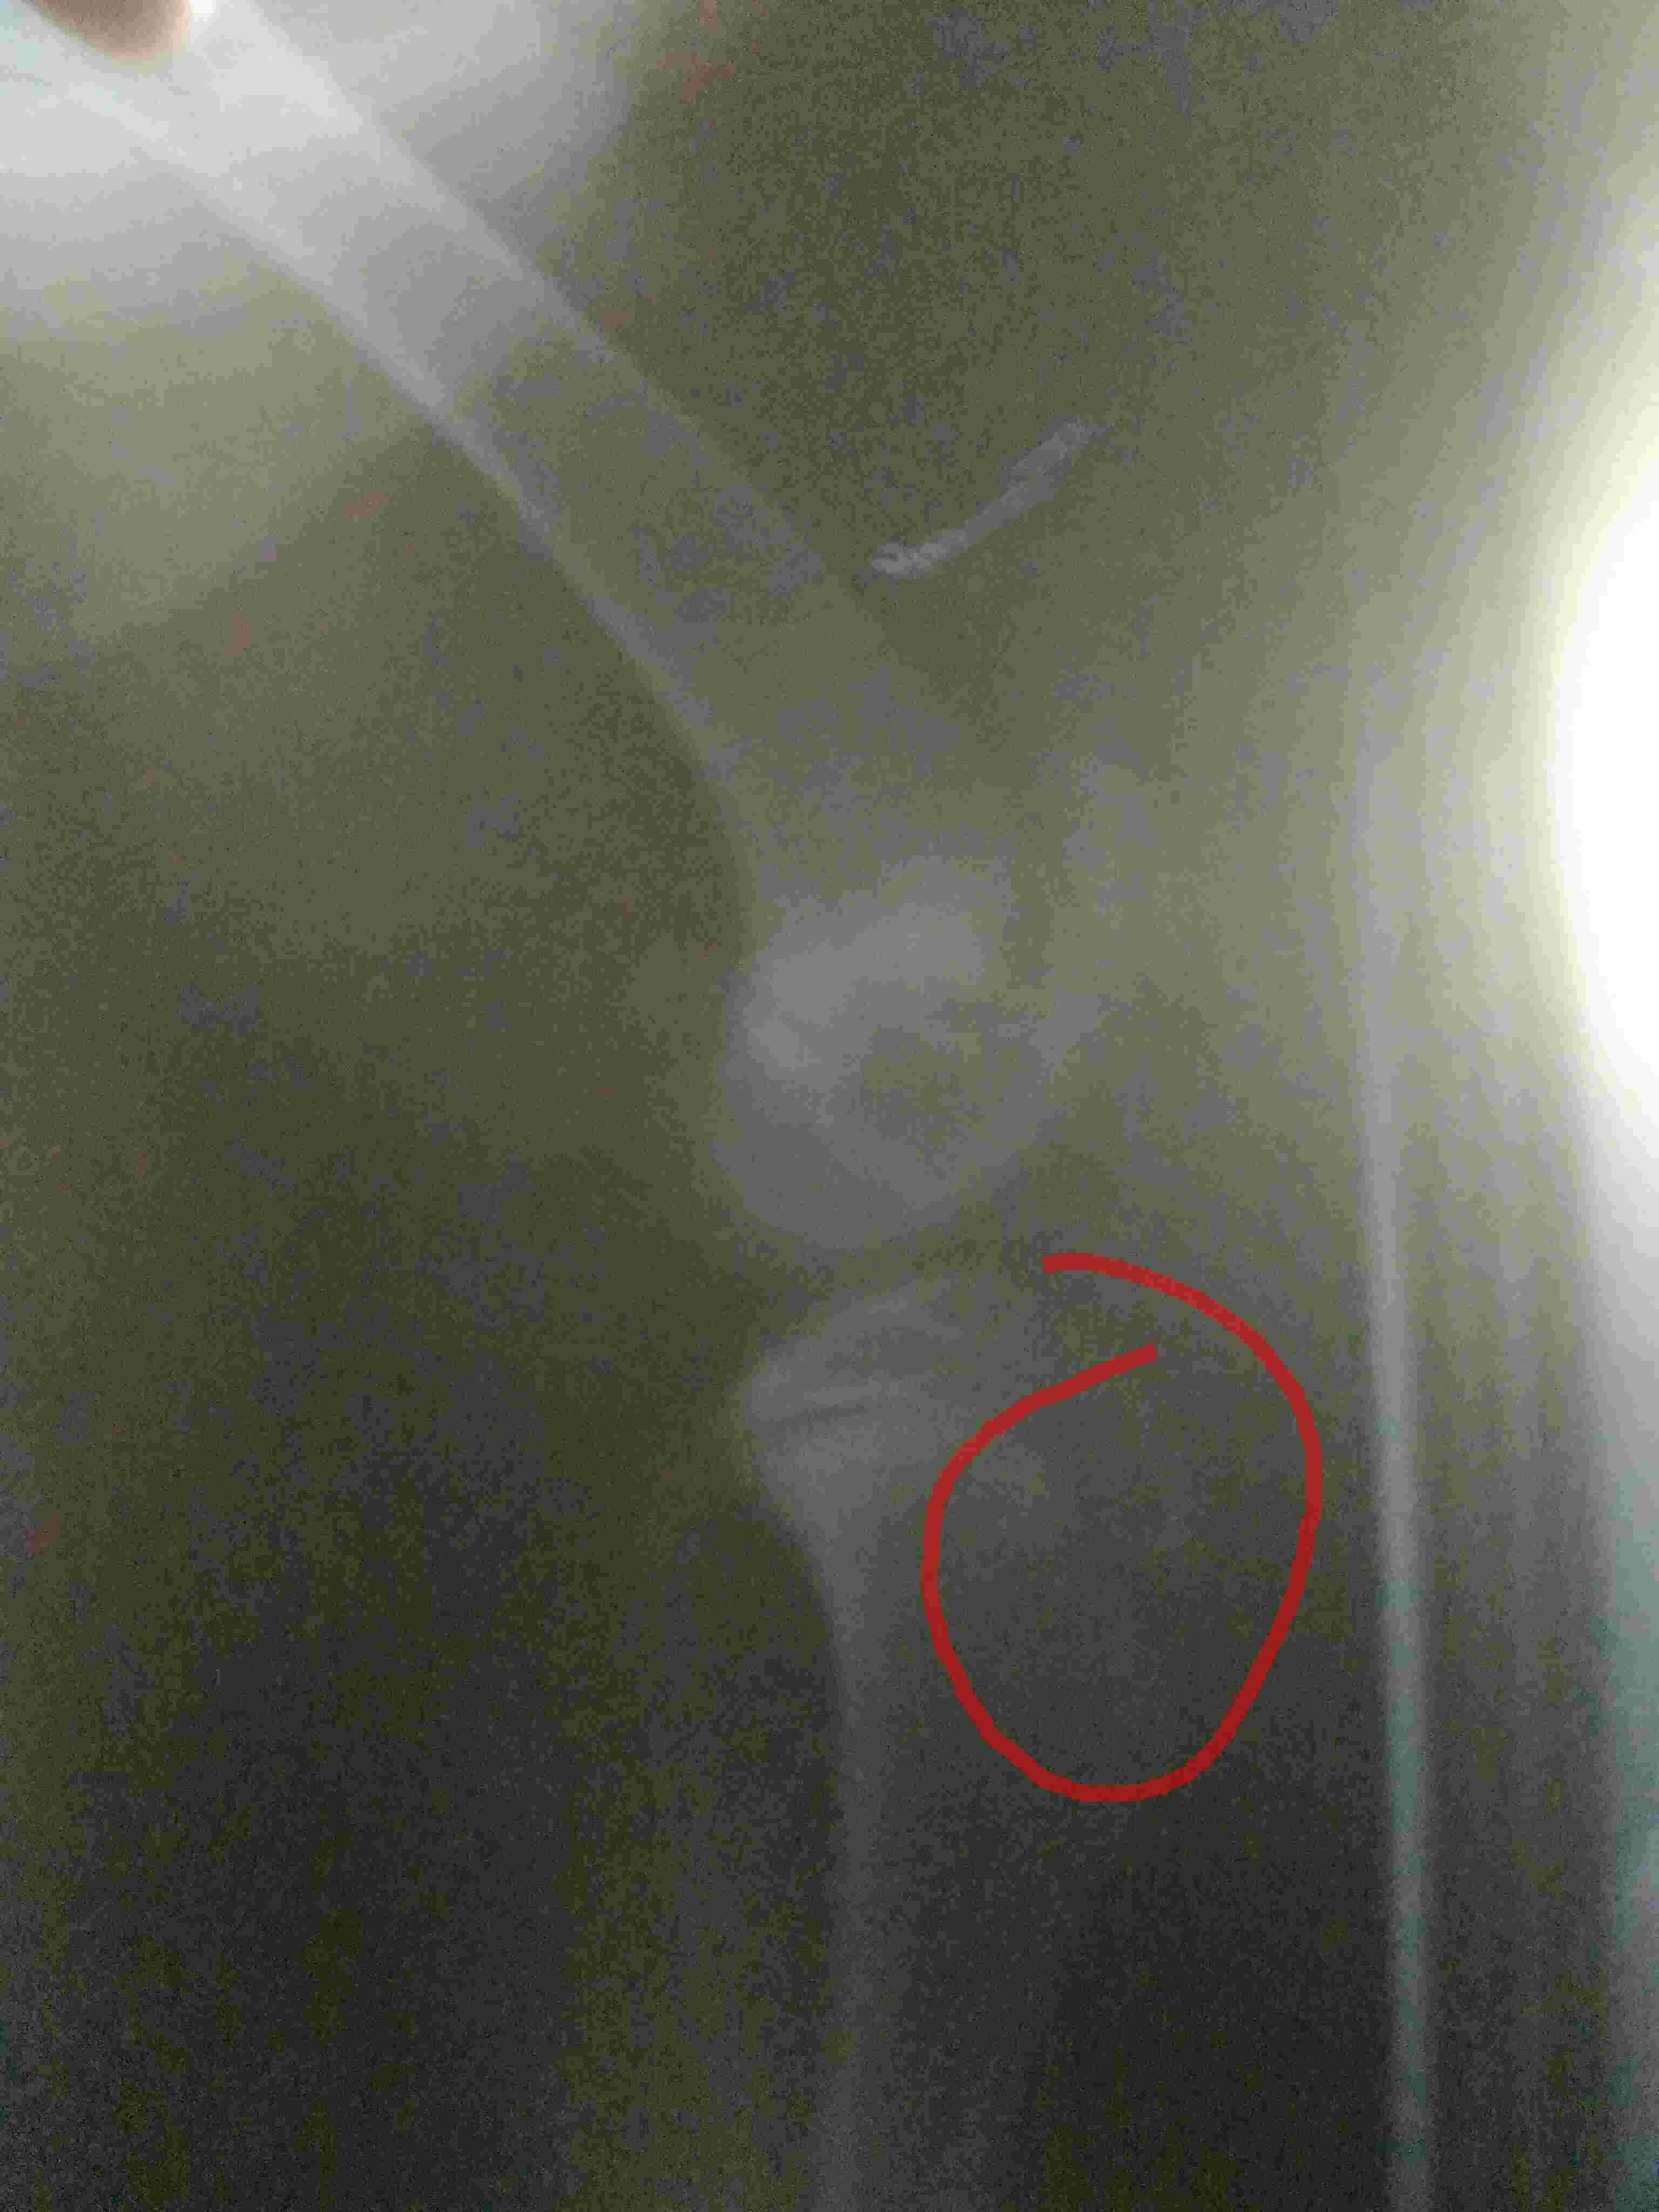

When she was about 2 to 3 months old ,once accidentally door got shut hitting n hurting her leg.Since then she was not walking properly,I took her to a vet ,they took an x ray ,said there was a little break in the bone and prescribed only calcium tablets saying as it is still young it will join automatically,but still she is not walking properly and they say there is no problem. . .I am confused . .

It is hard to evaluate on those x-rays but if she is still lame and having problems then you should go to another vet for a second opinion. You could also go to a veterinary orthopedic surgeon if there is one in your area. A specialist has more experience and will be able to evaluate your dog better.